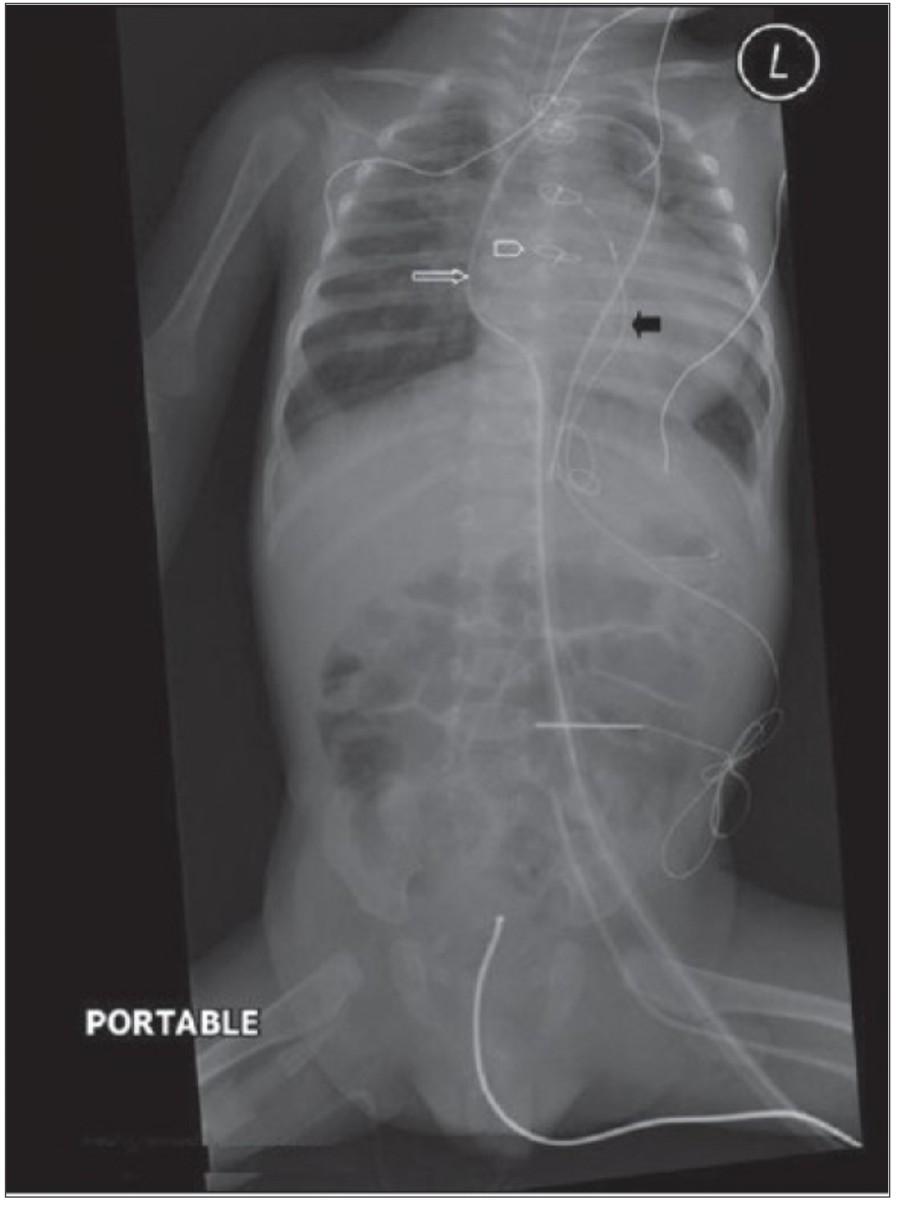

The thoracostomy tube

Supine AP radiograph에서 air는 anterior에, fluid는 중력에 의해 posterior에 위치하는 걸 인지하고 있어야 한다. Tube가 anterior에 위치하는지 아니면 posterior에 위치하는지는 단 한 장의 AP 사진으로 알기는 어렵다.

Pleural fissure 안에 위치하는 chest tube는 폐 표면이 늘어날 때 종종 배액이 안될 수 있으므로 적절히 기능을 하기 위해서 thoracic cavity 안에 거치되어야 한다. 마지막 side-hole은 radiopaque line의 interruption으로 확인할 수 있는데, 이 지점은 반드시 thoracic cavity 안에 위치해야 한다. Thoracic cavity 밖에 위치하거나 subcutaneous air가 확인되는 경우에 tube가 잘못 들어가 있음을 시사한다. Empyema에서 tube가 제대로 들어가 있지 않다면 배액이 잘 안 되거나 purulent fluid의 loculation이 발생하게 된다.

The feeding tube

Nasogastric tube 삽입은 의식이 없는 환자나 bronchial tree로 들어갈 위험이 높을 때는 chest X ray를 확인해야 한다. 또한 small-bore feeding tube를 삽입하거나 esophagectomy 환자에서 tube를 넣을 때도 chest X ray 확인이 필요하다. NG tube의 lower tip은 보통 abdominal radiograph로서 확인할 수 있다.